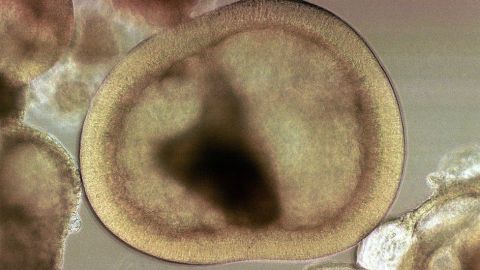

Las células madre embrionarias, que se extraen de un embrión en crecimiento, tienen la ventaja natural de poder dar lugar a cualquier otra célula del cuerpo, un atributo conocido como pluripotencia.

Embriones congelados

(Foto: Getty Images)